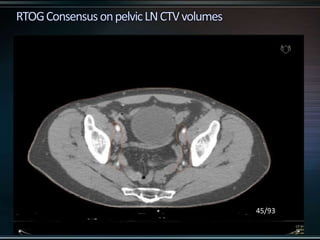

RTOG GU Consensus on pelvic LN CTV volumes:

 Commence contouring the pelvic CTV LN volumes at the L5/ S1

interspace (the level of the distal common iliac and proximal

presacral lymph nodes).

 Place a 7-mm margin around the iliac vessels connecting the

external and internal iliac contours on each slice, carving out

bowel, bladder, and bone.

 Contour presacral lymph nodes from S1 through S3, posterior

border being the anterior sacrum, and anterior border

approximately 10 mm anterior to the anterior sacral bone

carving out bowel, bladder, and bone.

 Stop external iliac CTV lymph node contours at the top of the

femoral heads (bony landmark for the inguinal ligament).

 Stop contours of the obturator CTV lymph nodes at the top of

the symphysis pubis.

RTOG GU Consensuson pelvic LN CTV volumes:  Commence contouring the pelvic CTV LN volumes at the L5/ S1 interspace (the level of the distal common iliac and proximal presacral lymph nodes).  Place a 7-mm margin around the iliac vessels connecting the external and internal iliac contours on each slice, carving out bowel, bladder, and bone.  Contour presacral lymph nodes from S1 through S3, posterior border being the anterior sacrum, and anterior border approximately 10 mm anterior to the anterior sacral bone carving out bowel, bladder, and bone.  Stop external iliac CTV lymph node contours at the top of the femoral heads (bony landmark for the inguinal ligament).  Stop contours of the obturator CTV lymph nodes at the top of the symphysis pubis.